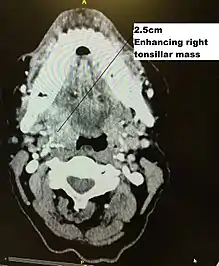

| Diagnostic method | Endoscopy, Biopsy, Staining for p16, CT Scan, |

Staging is generally by the UICC/AJCC TNM (Tumour, Nodes, Metastases) system.[68] Staging is based on clinical examination, diagnostic imaging, and pathology. On imaging, involved lymph nodes may appear cystic, a characteristic of HPV+OPC.[69]